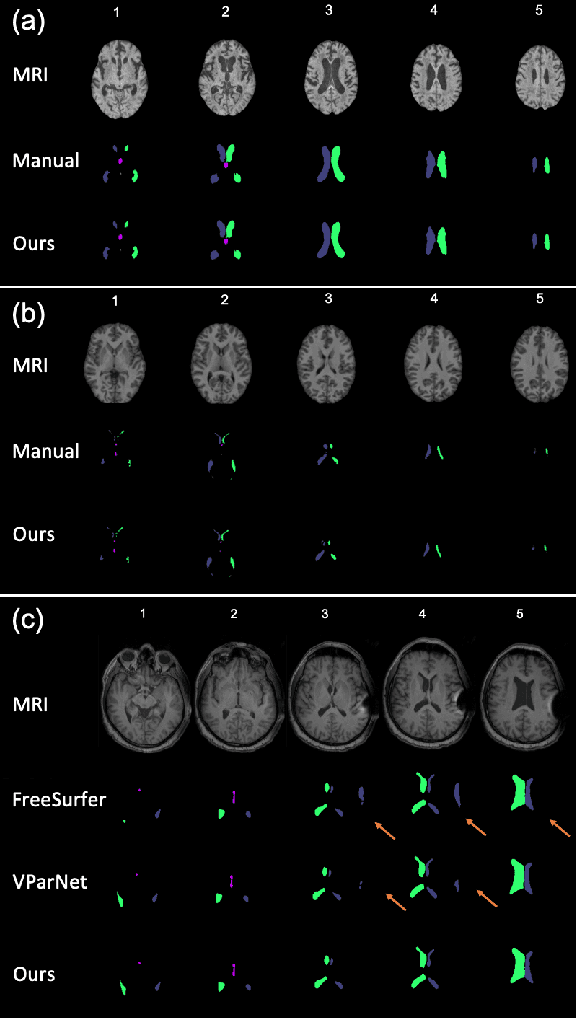

Abstract:Normal pressure hydrocephalus~(NPH) is a brain disorder associated with enlarged ventricles and multiple cognitive and motor symptoms. The degree of ventricular enlargement can be measured using magnetic resonance images~(MRIs) and characterized quantitatively using the Evan's ratio (ER). Automatic computation of ER is desired to avoid the extra time and variations associated with manual measurements on MRI. Because shunt surgery is often used to treat NPH, it is necessary that this process be robust to image artifacts caused by the shunt and related implants. In this paper, we propose a 3D regions-of-interest aware (ROI-aware) network for segmenting the ventricles. The method achieves state-of-the-art performance on both pre-surgery MRIs and post-surgery MRIs with artifacts. Based on our segmentation results, we also describe an automated approach to compute ER from these results. Experimental results on multiple datasets demonstrate the potential of the proposed method to assist clinicians in the diagnosis and management of NPH.